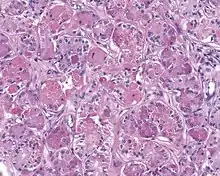

High power H&E stained image of a parotid sclerosing polycystic adenoma with eosinophilic granules

When reviewed by a pathologist, the findings are quite similar to fibrocystic changes of the breast, although they are different enough, that it is now recognized to actually represent a true neoplasm (clonal proliferation) through various studies.[5] Specifically, the lesions are usually well-circumscribed, containing lobules of haphazardly arranged ducts, myoepithelial cells, and acini that have abundant sclerosing or hyalinized fibrosis. Apocrine change is quite common in the ductal cells.[6] The ducts range from small ductules to cystically dilated spaces (more than 4 striated duct-widths across), often containing products of secretion or reactive histiocytes. A very curious and characteristic finding in all of the lesions is the presence of bright pink (eosinophilic) acinar granules (which are altered zymogen).